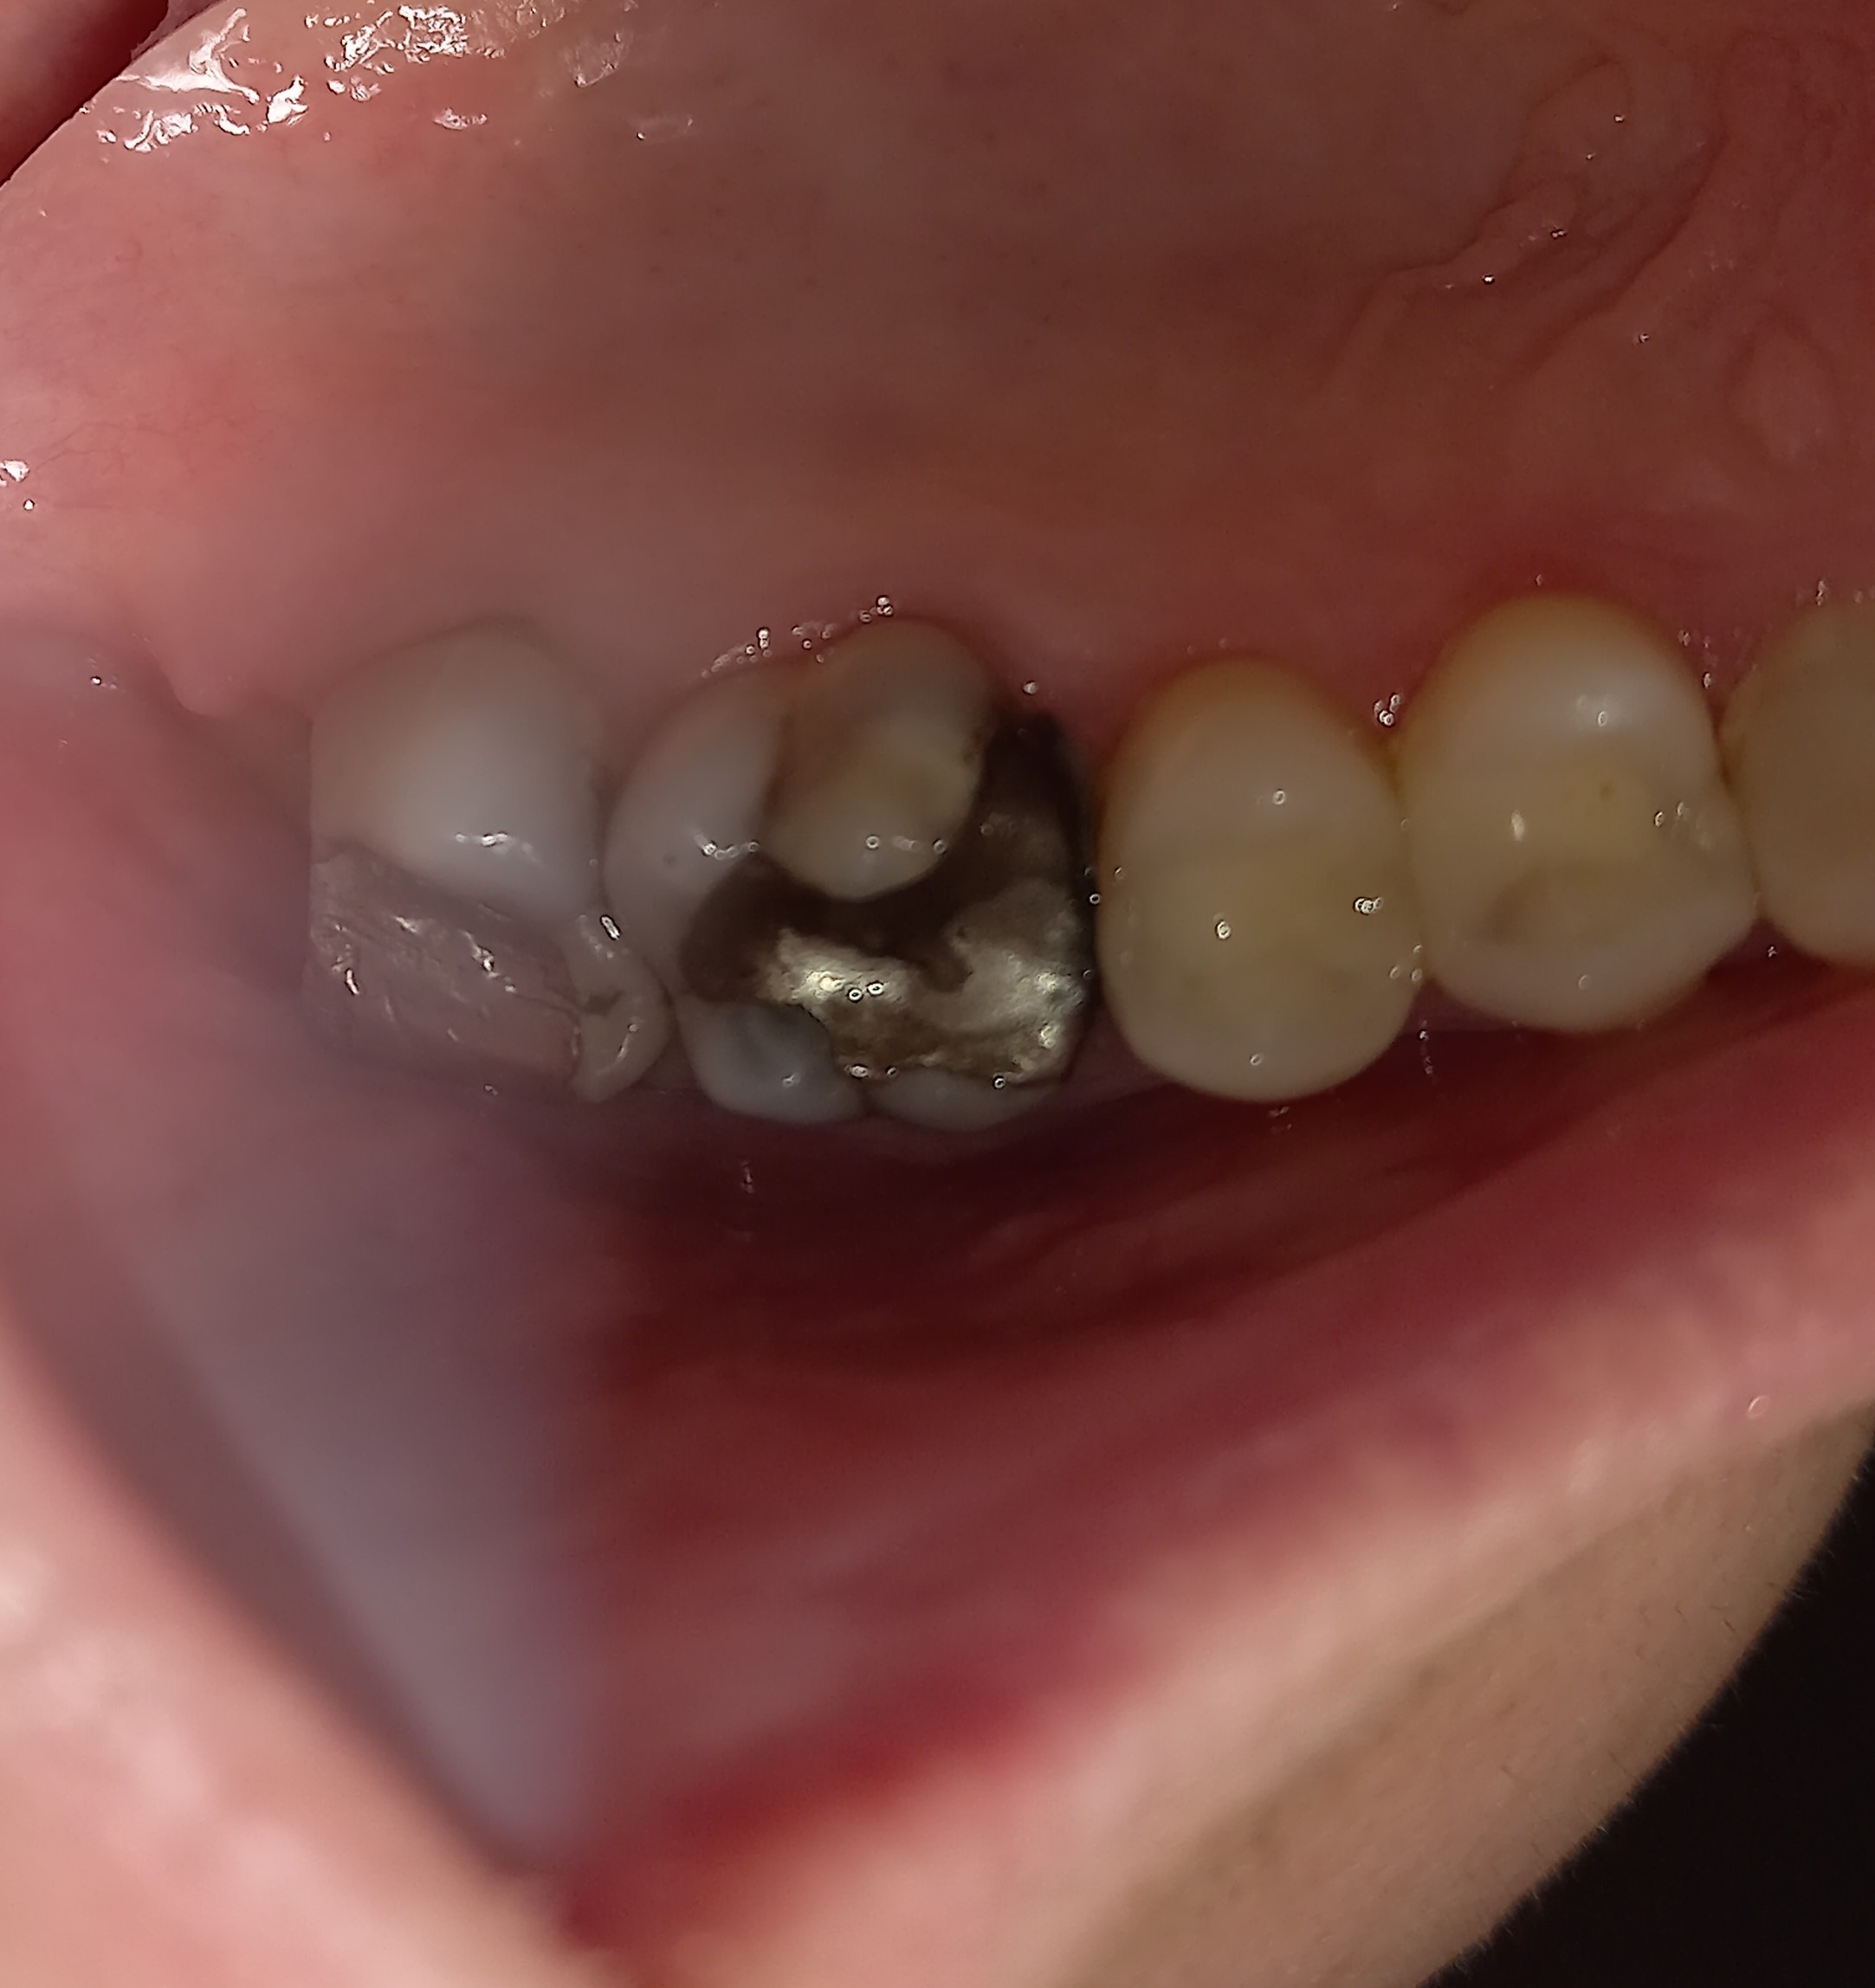

Η ασθενής επιθυμούσε να αντικαταστήσει 2 παλιά σφραγίσματα αμαλγάματος. Αποφασίστηκε η κατασκευή δύο ολοκεραμικών θηκών. Σύμφωνα με το γερμανικό πρωτόκολλο για τις απονευρώσεις δοντιών, πριν από μία προσθετική δουλειά θα πρέπει να ελέγχονται παλιές απονευρώσεις που υπάρχουν ήδη σε ένα δόντι. Σε περίπτωση που αυτές είναι αμφιλεγόμενες, τότε ενδείκνυται η επανάληψη απονεύρωσης, ώστε να μην προκύψουν στο μέλλον προβλήματα με το δόντι ενώ θα έχει κολληθεί η προσθετική δουλειά.

Στο συγκεκριμένο περιστατικό πραγματοποιήθηκε επανάληψη απονεύρωσης στο πρώτο δεξιό γομφίο. Στη διάρκεια της διαδικασίας εντοπίστηκε και τέταρτος ριζικός σωλήνας, ο οποίος δεν είχε βρεθεί στην πρώτη παλιά απονεύρωση. Η εγγύς ρίζα είχε ενασβεστιωθεί με τα χρόνια και δεν ήταν δυνατόν να επεξεργαστεί ο ριζικός σωλήνας σε όλο το μήκος του. Όμως όλες οι ρίζες παρασκευάστηκαν και καθαρίστηκαν πολύ καλά και στη συνέχεια εμφράχθηκαν ερμητικά.

ΠΡΙΝ – Παλιά μαύρα σφραγίσματα